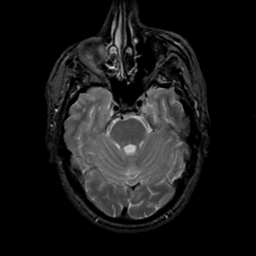

MR Study #22, December 1, 1991 -- Slice #15

[Home][Help][Clinical][Tour 1][Tour 2] Slice 15